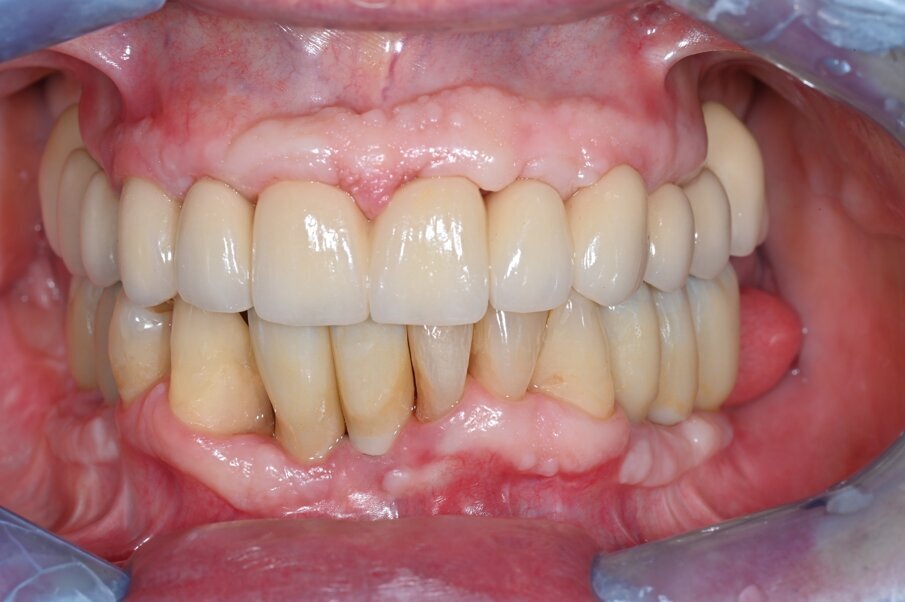

È stata realizzata una riabilitazione full-arch con framework in cromo medicale e rivestimento in ceramica. Il corretto accoppiamento e la passività della struttura protesica sono stati valutati clinicamente e radiograficamente. Le viti protesiche di fissaggio sono state serrate ad un torque di 30N/cm (Figg. 5a, 5b).

Fig. 5a_Visione frontale della riabilitazione protesica definitiva.

Fig. 5b_Visione occlusale della riabilitazione protesica definitiva.

I controlli clinici e radiografici a 4 anni hanno mostrato un’ottima stabilità della riabilitazione con assenza di infiammazione e patologia a carico dei tessuti duri e molli peri implantari (Figg. 6-7c). La stabilità dei margini ossei perimplantari è stata valutata con radiografie endorali che hanno evidenziato assenza di riassorbimento osseo patologico. La sistematica descritta non ha presentato complicanze biologiche o meccaniche nel periodo di osservazione, con soddisfazione dei criteri di successo perimplantare.

Fig. 6_Follow up a 4 anni: visione frontale della riabilitazione definitiva a 4 anni.